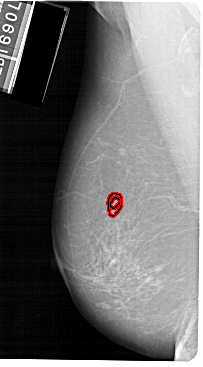

A_1149_1.LEFT_MLO

FILE: A_1149_1.LEFT_MLO.OVERLAY

TOTAL_ABNORMALITIES 1

ABNORMALITY 1

LESION_TYPE MASS SHAPE IRREGULAR MARGINS SPICULATED

ASSESSMENT 4

SUBTLETY 2

PATHOLOGY MALIGNANT

TOTAL_OUTLINES 2

BOUNDARY

CORE